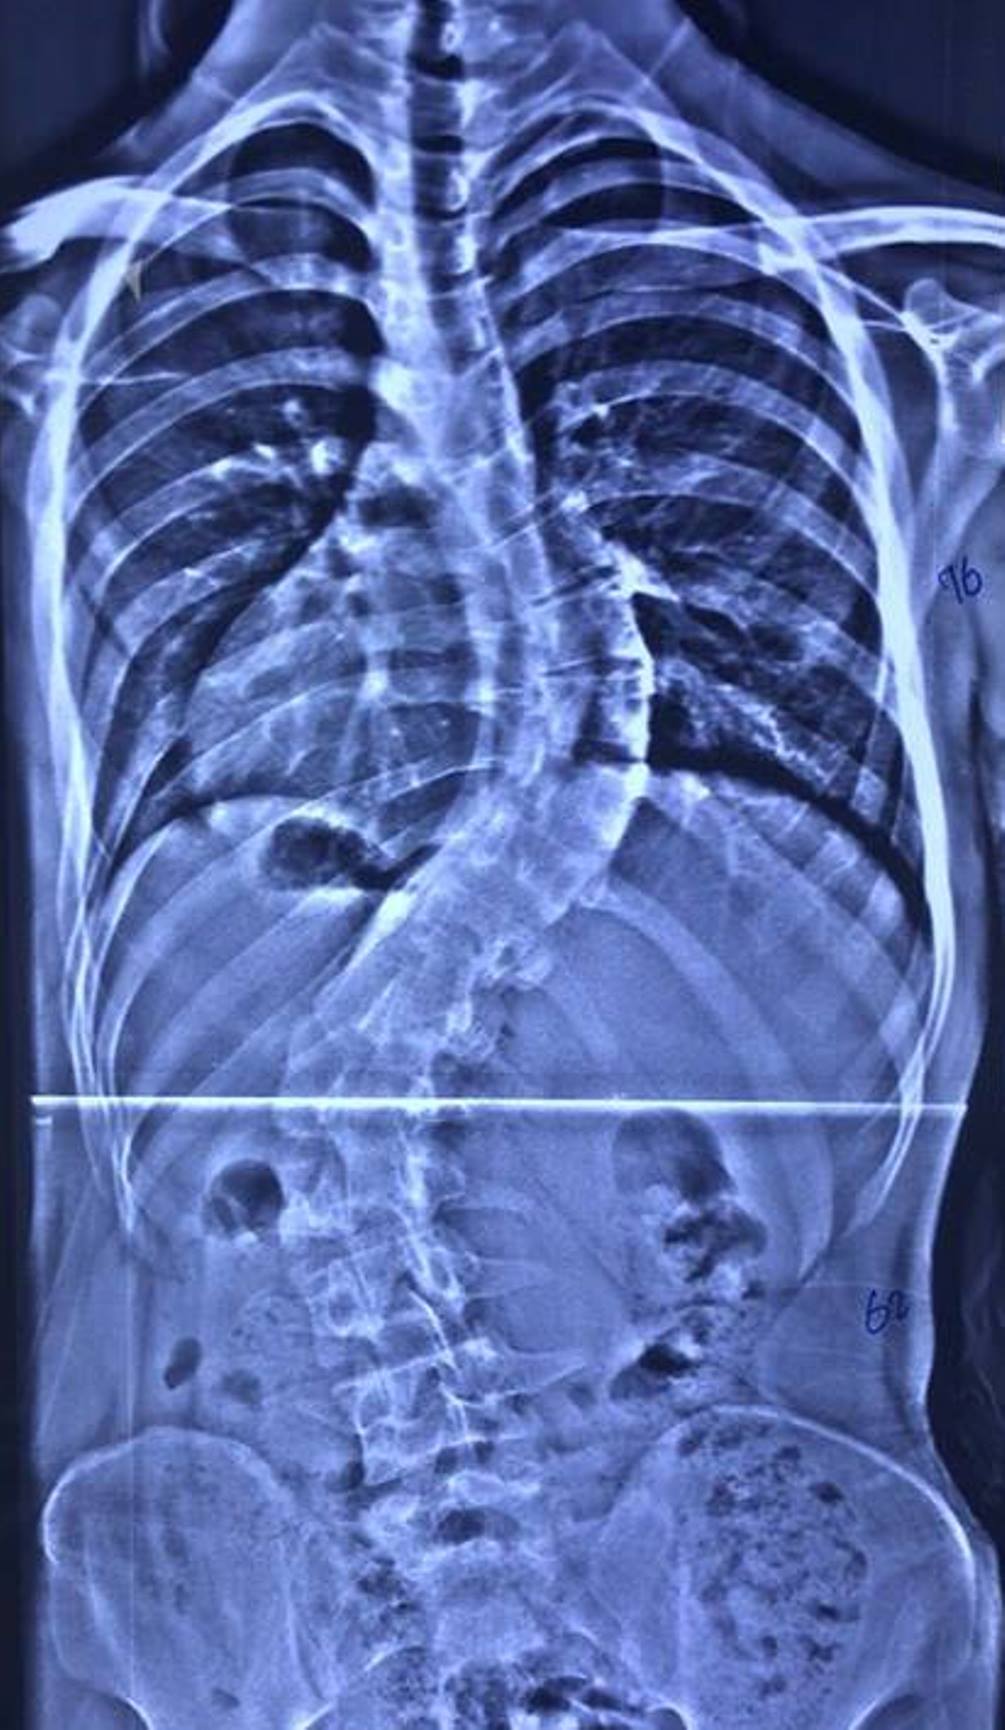

وقال إختصاصي جراحة العمود الفقري بالمستشفى الطبيب اللبناني، دكتور عامر السبعلي، في حديث صحافي، إن فريقنا الطبي نجح بعملية تعديل جنف العمود الفقري (إنحراف وتحدب العمود الفقري) لمريضة تبلغ من العمر (63) عاما، مبيناً إن الجنف بنسبة (35%)، وإن المريضة تعاني من تضييق في مجرى الدودة يرافقه آلام حادة جعلتها غير قادرة على ممارسة حياتها بشكل طبيعي.

وأشار السبعلي إلى، إن العملية إستغرقت خمس ساعات، بمساعدة فريق طبي متميز وأطباء تخدير ماهرين، فضلاً عن وجود التقنيات الحديثة التي شجعتنا على إجراء العملية، مؤكداً إن العملية كانت ناجحة والمريضة أستعادت إستقامة ظهره عقبها وهي الآن تتمتع بصحة جيدة.